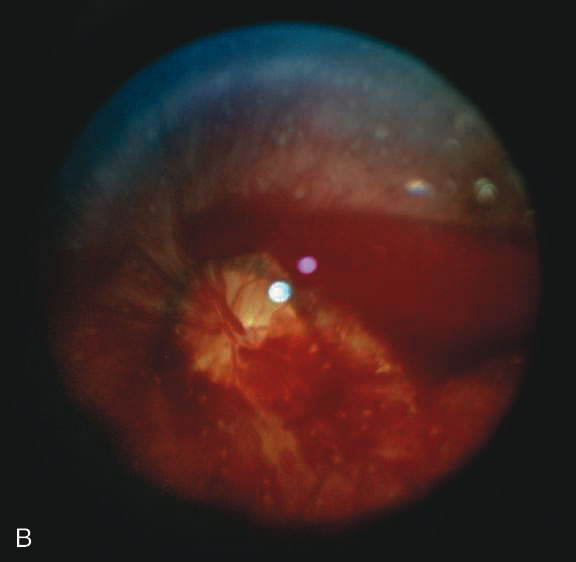

Findings range from a normal fundus to a small number of scattered intraretinal hemorrhages in the posterior pole to massive, confluent hemorrhages from the posterior pole to the ora serrata.(Fig. 10) The hemorrhages may be subretinal, deep intraretinal (dot/blot), nerve fiber layer (flame shaped) or preretinal.19,45 Intraretinal hemorrhages are more common than preretinal or subretinal hemorrhages.32,46 Preretinal hemorrhages must be distinguished from traumatic retinoschisis (see later), which has particular diagnostic significance. White-centered retinal hemorrhages, although classically associated with endocarditis, can occur in any condition that causes retinal hemorrhages, including SBS. Vitreous hemorrhage may be small to massive, and may occur secondary to escape of blood from intraretinal collections or from torn vessels.19 Although vitreous hemorrhage may occur at the time of injury, it may also be a delayed finding occurring 1 to 3 days or more after the initial trauma.47,48

Fig. 10. Retinal hemorrhages in SBS may range from a nonspecific mild posterior pole distribution (10A) to a more characteristic picture of too numerous to count, multiple, extensive intraretinal hemorrhages (in this many with white centers) with subhyaloid hemorrhage (10B, 10C)